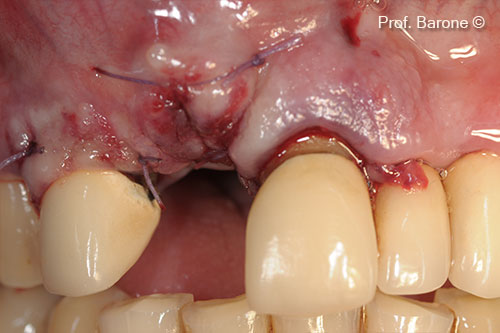

Soft tissue primary closure

Soft Tissue Healing after 6 months